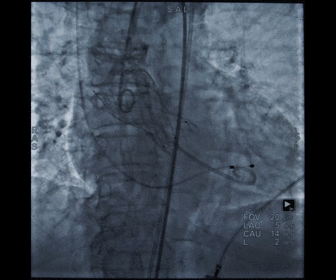

造影观察瓣膜形态

术后造影及超声探查未见瓣周漏,跨瓣压差术前47mmHg,术后几乎无压差,术中及术后未出现相关并发症,手术圆满完成。